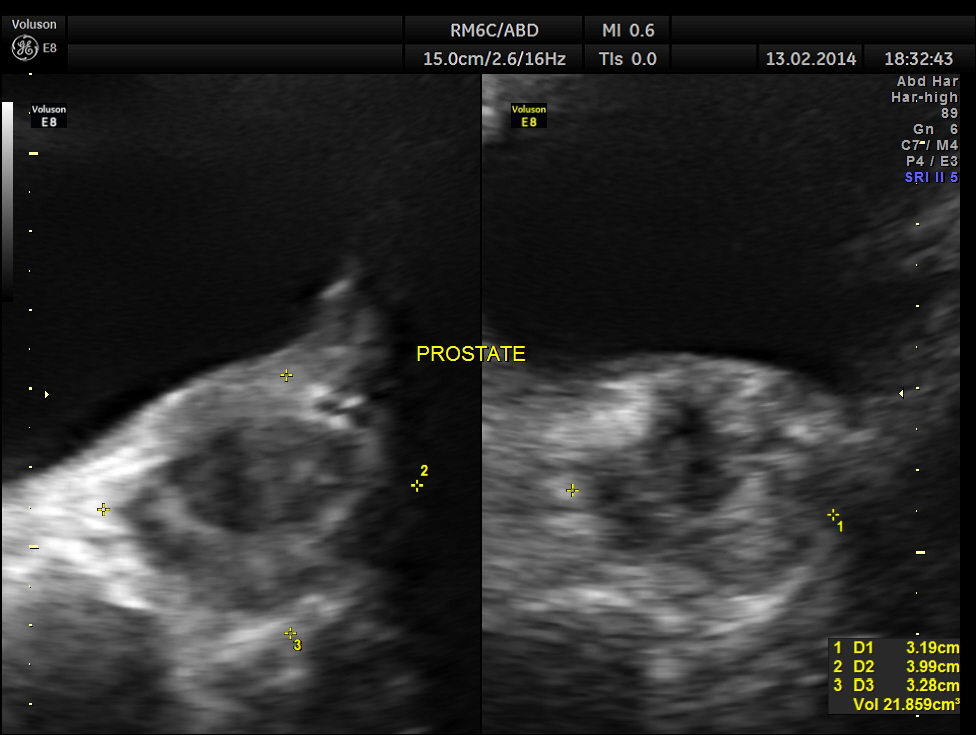

mildly enlarged prostate